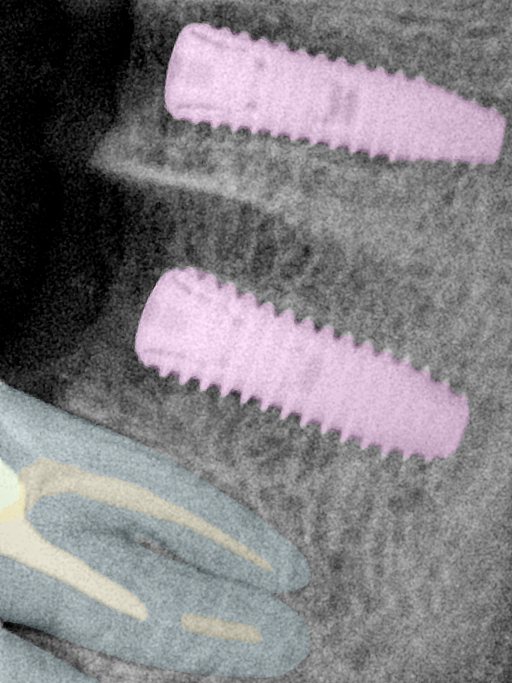

CR/DR 牙齿分割阶段记录

当前进展

- 完成了 CR/DR 牙齿相关分割训练

- 当前结果已经达到阶段预期,但仍有细节问题需要继续处理

相关测试

遇到的问题

- 训练过程中出现过 mask 下移问题

- 部分结果会出现 box 填充异常

- mask 边缘仍然有比较明显的锯齿感